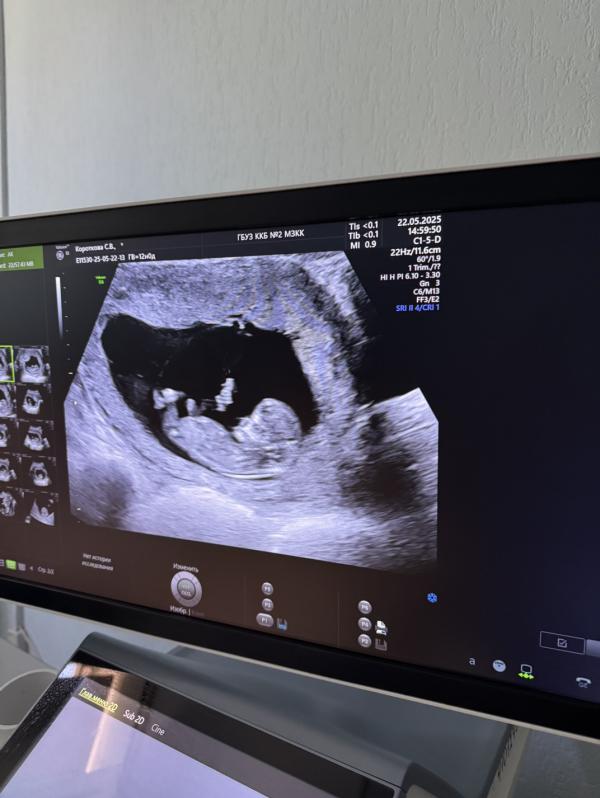

Сегодня был долгожданный первый скрининг.

Так как я стараюсь усмирять свою тревожность и не бегаю на узи каждую неделю, последний раз я там видела совсем крошечный эмбрион, а теперь настоящий маленький человечек😍

Стою на учете в ЖК5, попадалось здесь много постов про то как там проходят узи и настроилась уже на то что даже монитор не покажут, но как же я ошибалась. Врач Саакян Х.Э просто золотко, всё что видит комментировала, экран показала и сама предложила фоток сделать, все детально описала, вежливая и доброжелательная, я очень рада что попала именно к ней и у меня не испортилось впечатление от такого важного для меня события